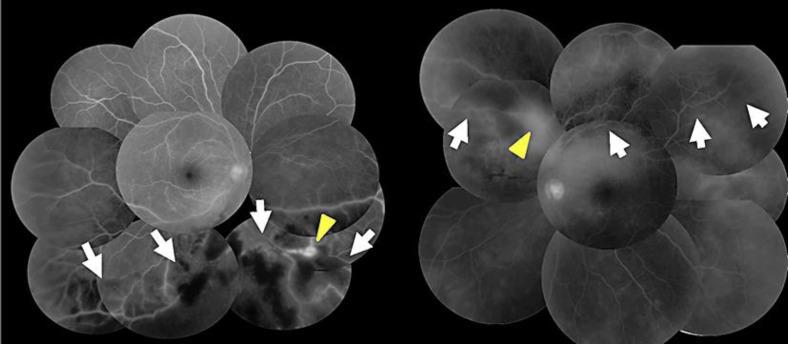

We report a rare case of syphilitic intraocular inflammation with occlusive retinal vasculitis treated with intravitreal injection of bevacizumab (IVB) in addition to conventional therapy for syphilis.

A 24-year-old woman who complained floaters in both her eyes showed occlusive retinal vasculitis OU. According to the high titer of the Treponema antigen and characteristic cutaneous eruption, she was diagnosed as secondary syphilis.

She was treated with oral amoxicillin and retinal photocoagulation OU. Then, administration of prednisolone was required to the intraocular inflammations considered as Jarisch-Herxheimer reactions. IVB was also performed toward exacerbated retinal neovascularization and showed transient effects.

We experienced a rare case of occlusive retinal vasculitis accompanied by syphilis intraocular inflammation. IVB was considered to be effective as an adjunctive therapy for inflammatory neovascularizations.